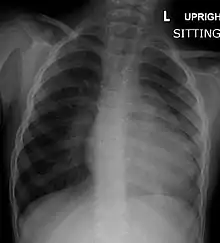

Chest radiograph

Before more sophisticated techniques became available, chest X-ray was the definitive method of diagnosis. The abnormal "coeur-en-sabot" (boot-like) appearance of a heart with tetralogy of Fallot is classically visible via chest X-ray, although most infants with tetralogy may not show this finding.[51] The boot like shape is due to the right ventricular hypertrophy present in TOF. Lung fields are often dark (absence of interstitial lung markings) due to decreased pulmonary blood flow.[52]: 171–72

| Right ventricular hypertrophy | The right ventricle is more muscular than normal, causing a characteristic boot-shaped (coeur-en-sabot) appearance as seen by chest X-ray. Due to the misarrangement of the external ventricular septum, the right ventricular wall increases in size to deal with the increased obstruction to the right outflow tract. This feature is now generally agreed to be a secondary anomaly, as the level of hypertrophy tends to increase with age.[46] |